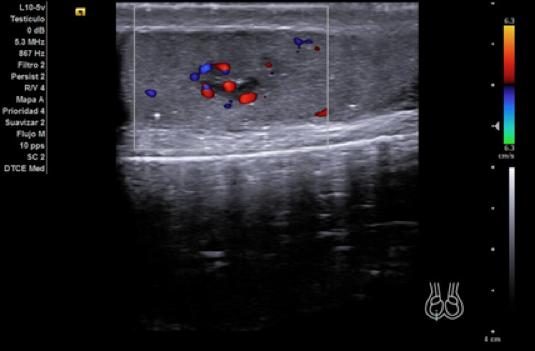

Hallazgos ecográficos

Ecografía Clinica: testículo izquierdo de tamaño y ecogenicidad normales, con microcalcificaciones y colas de cometa. Testículo derecho más pequeño que el contralateral, y en su zona central una lesión hipoecoica lobulada e irregular con captación intralesional y calcificaciones puntiformes en parénquima testicular. Con la sospecha de una neoplasia del testículo derecho se consulta con Urología, que solicita analítica y cita.

Los marcadores tumorales (LDH, BHCG, alfafetoproteína) son negativos y la ecografía se repite de forma reglada para descarte de neoplasia testicular. En esta última se define un teste derecho disminuido de tamaño y ecoestructura heterogénea, con áreas centrales hipoecogénicas aunque sin lesiones claramente definidas.

El diagnóstico de sospecha tras ser evaluado por Urología es una atrofia testicular derecha. En el diagnóstico diferencial se debe incluir la posibilidad de que la atrofia sea por una torsión testicular previa, una orquitis u orquiepididimitis que cause atrofia secundaria, traumatismos, infartos testiculares no traumáticos y neoplasia testicular. La ecografía clínica tiene parte de concordancia con la reglada, sin embargo, en esta última no se define la lesión hipoecoica lobulada e irregular que nos hace sospechar en AP que pueda tratarse de una lesión tumoral.